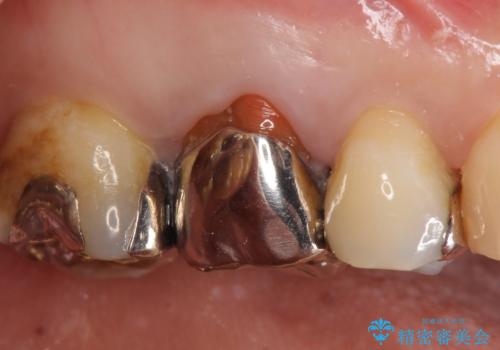

炎症が急性化し、歯ぐきの裏は膿で大きく腫れあがっていたため、切開・排膿・ガーゼドレーンにより腫れを落ちつかせた後(Dr奥村に協力してもらいました)、精密根管治療を行いました。

プラスチックを全て除去したことで、本来の歯の形態は失われるため、根管治療後の封鎖も兼ねて、被せもので修復します。

治療後、レントゲンでも根の先にあった病気が治癒し、骨に置換されているのがわかります。

被せものの種類:ジルコニアオールセラミック スタンダード